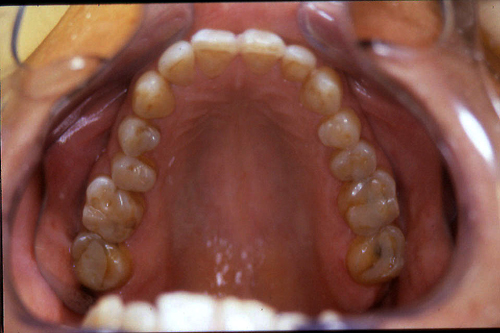

ABSTRACT El Bruxismo es una entidad patológica en la que concurren diferentes factores. Entre ellos el stress que conlleva consigo la vida moderna, constituye el Factor Predisponente sobre el que se ha abundado en innumerables tratamientos de tipo general, actuando sobre la psiquis y el comportamiento del individuo, ya sea con fármacos o bien mediante medios psicológicos. Sin embargo, como tantos desequilibrios provocados por el stress, confluyen siempre con un Factor Desencadenante, que en el caso del Bruxismo se encuentra en las desarmonías entre los componentes varios del Sistema Estomatognático. DESARROLLO Paciente varón, de 43 años, constitución atlética. A la inspección se observan desgastes oclusales que alcanzan la calidad de Facetas Parafuncionales, con dentina expuesta y empastes totalmente gastados y evidentes signos de falta de Disclusión Canina de ambos lados. Sobre dicho montaje se realiza un Encerado Progresivo de Diagnóstico, aportando en el mismo los elementos necesarios para obtener todos los principios básicos de una Oclusión Orgánica. FIG. 6 a 24 Una vez aprobado el fisiologismo de la oclusión en el articulador, se reproducen modelos de yeso con la nueva situación, y se estampa un SET UP en cada maxilar. FIG. 25/26 Procedemos entonces al tallado de las piezas correspondientes a la Guía Anterior, y rebasamos los estampados, creando en boca una nueva situación desoclusiva, que permanece en boca durante los pocos días que transcurren entre la primera y segunda visita de trabajo. FIG. 27/33 Ya abordando en esta segunda visita los sectores posteriores, tanto superiores como inferiores, tallamos siempre de manera supragingival, destacando la importancia vital de la forma obtenida en las provisionales, a las que abrimos plenamente las troneras para lograr una correcta higiene. FIG.34 a 43 FIG. 44 a 52 Efectuados los colados en oro y probados en boca, en el laboratorio se confecciona el bizcochado de la nueva Guía Anterior, la que puede o no copiarse de la Guía Anterior provisional, mediante la técnica denominada Trayectoria Funcionalmente Generada, que consiste en realizar en la platina del articulador un registro estereográfico sobre acrílico Duralay en polimerización. FIG. 57/58 Ajustados todos los detalles mediante esta técnica, se instala en boca en forma Provisional y se deja funcionando una semana o dos, al cabo de las cuales se chequean las disclusiones , los ajustes, la eficacia masticatoria, la carencia de sintomatología articular y muscular. FIG.59 a 63 PIE DE FOTO FIG.9 OBTENCIÓN DE LA GUÍA ANTERIOR FIG.10 Y 11 PITOMBOS. ALINEAC. TRIDIMENSIONAL FIG.12 PITOMBOS. DISCLUSIÓN DER. FIG.13 PITOMBOS. DISCLUSIÓN IZQ. FIG.14 WILSON INF. FIG.15 WILSON SUP. FIG.16 BOCA DE PEZ INF. FIG.17 BOCA DE PEZ SUP. FIG.18 VISTA OCLUSAL FIG.19 O.R.C. FIG.20 DISCLUSIÓN DERECHA FIG.21 CRESTAS TRIANG. INT. FIG.22 CRESTAS TRIANG. INT. FIG.23 CRESTAS TRIANG. INT. FIG 24 CRESTAS TRIANG. INT. FIG.59 DISCLUSIÓN IZQ. FIG.60 DISCLUSION IZQ. FIG.61 DISCLUSIÓN DER. FIG.62 DISCLUSION DER. FIG. 63 AJUSTE PERIFÉRICO

Asiste a la consulta preocupado por sensibilidad dentaria ante el frío y el calor y por decoloraciones blanquecinas en sus dientes anteriores.

Con síntomas dolorosos y dinámicos en la ATM, con un estado periodontal sano y marcadas hipertrófias maseterinas.

Su condición de “borde a borde” también impide la disclusión en propulsiva, compartiendo en todas las excursiones las fuerzas con las piezas posteriores.